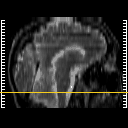

Click on sagittal image to select slice. Click on thin tickmark to change timepoint, or thick tickmark for overlay.